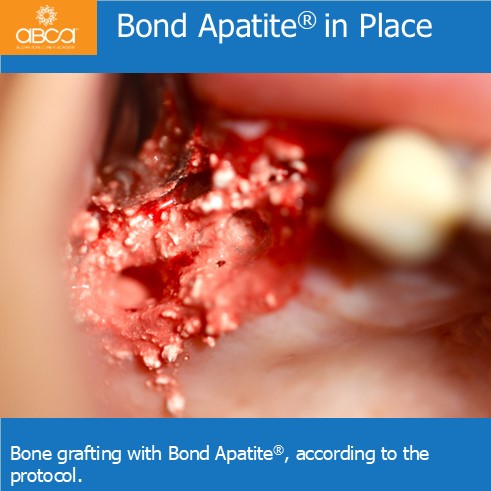

Sinus lift with Augma Lift™ Kit B with 4-5 mm sub sinus bone height.

Sinus lift with Augma Lift™ Kit B with 4-5 mm sub sinus bone height. A young woman came to replace the missing first maxillary molar with moderate atrophy.

Sinus lift with Augma Lift™ Kit B in a case with 5 mm sub sinus bone height.

Sinus lift with Augma Lift™ Kit B in a case with 5 mm sub sinus bone height. The patient came for implant treatment in the region of teeth #16 (3)…

Sinus lift with Augma Lift™ Kit B in a case with missing teeth #14 (5), #15 (4), #16 (3), #17 (2) and a sub sinus bone height of 6 mm.

Sinus lift with Augma Lift™ Kit B in a case with 6 mm sub sinus bone height.